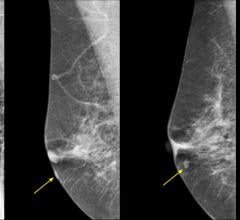

Breast density, or fibroglandular density, is found through breast imaging and compares the amount of fat to the amount of tissue.

At some point, every breast imager has one of those unsettling moments where they discover an advanced tumor and wonder ...